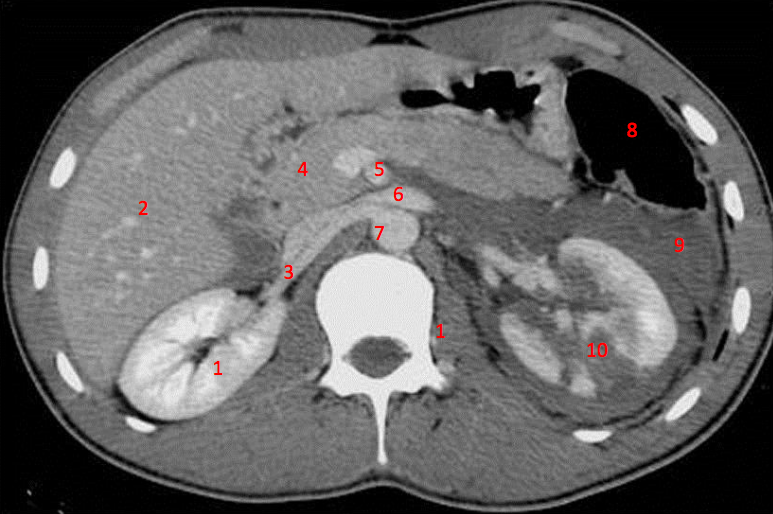

1

Number 3?

IVC

2

Number 1?

3

13

Number 4?

Head of pancreas

14

Rt diaghragmatic crus

16

Number 2?

17

Rt lobe liver

21

Number 5?

Rt ureter

22

Number 6?

Descending colon

23

Number 9?

Superior mesenteric artery

24

Number 8?

25

Number 7?

Abdominal aorta

26

Rt erector spinae muscle

27

Spleen

28

Rt renal artery

29

Lt common iliac artery

31

Portal vein

33

Falciform/round ligament

34

Haematoma

35

Hepatic flexure

36

Splenic vein

39

40

Lt iliac blade/ilium

41

L Ventricle

42

Rt psoas

43

Rt oblique muscle

44

Rt rectus abdonimalis muscle

45

Rt psoas muscle

46

Lt renal vein

47

Number 10?

Rt kidney

48

Duodendum

49

Aorta

50

Ascending colon

51

Rt gluteus muscle

52

Traumatic laceration of Lt kidney

53

Lt erectae spinae muscle

54

55

Caecum